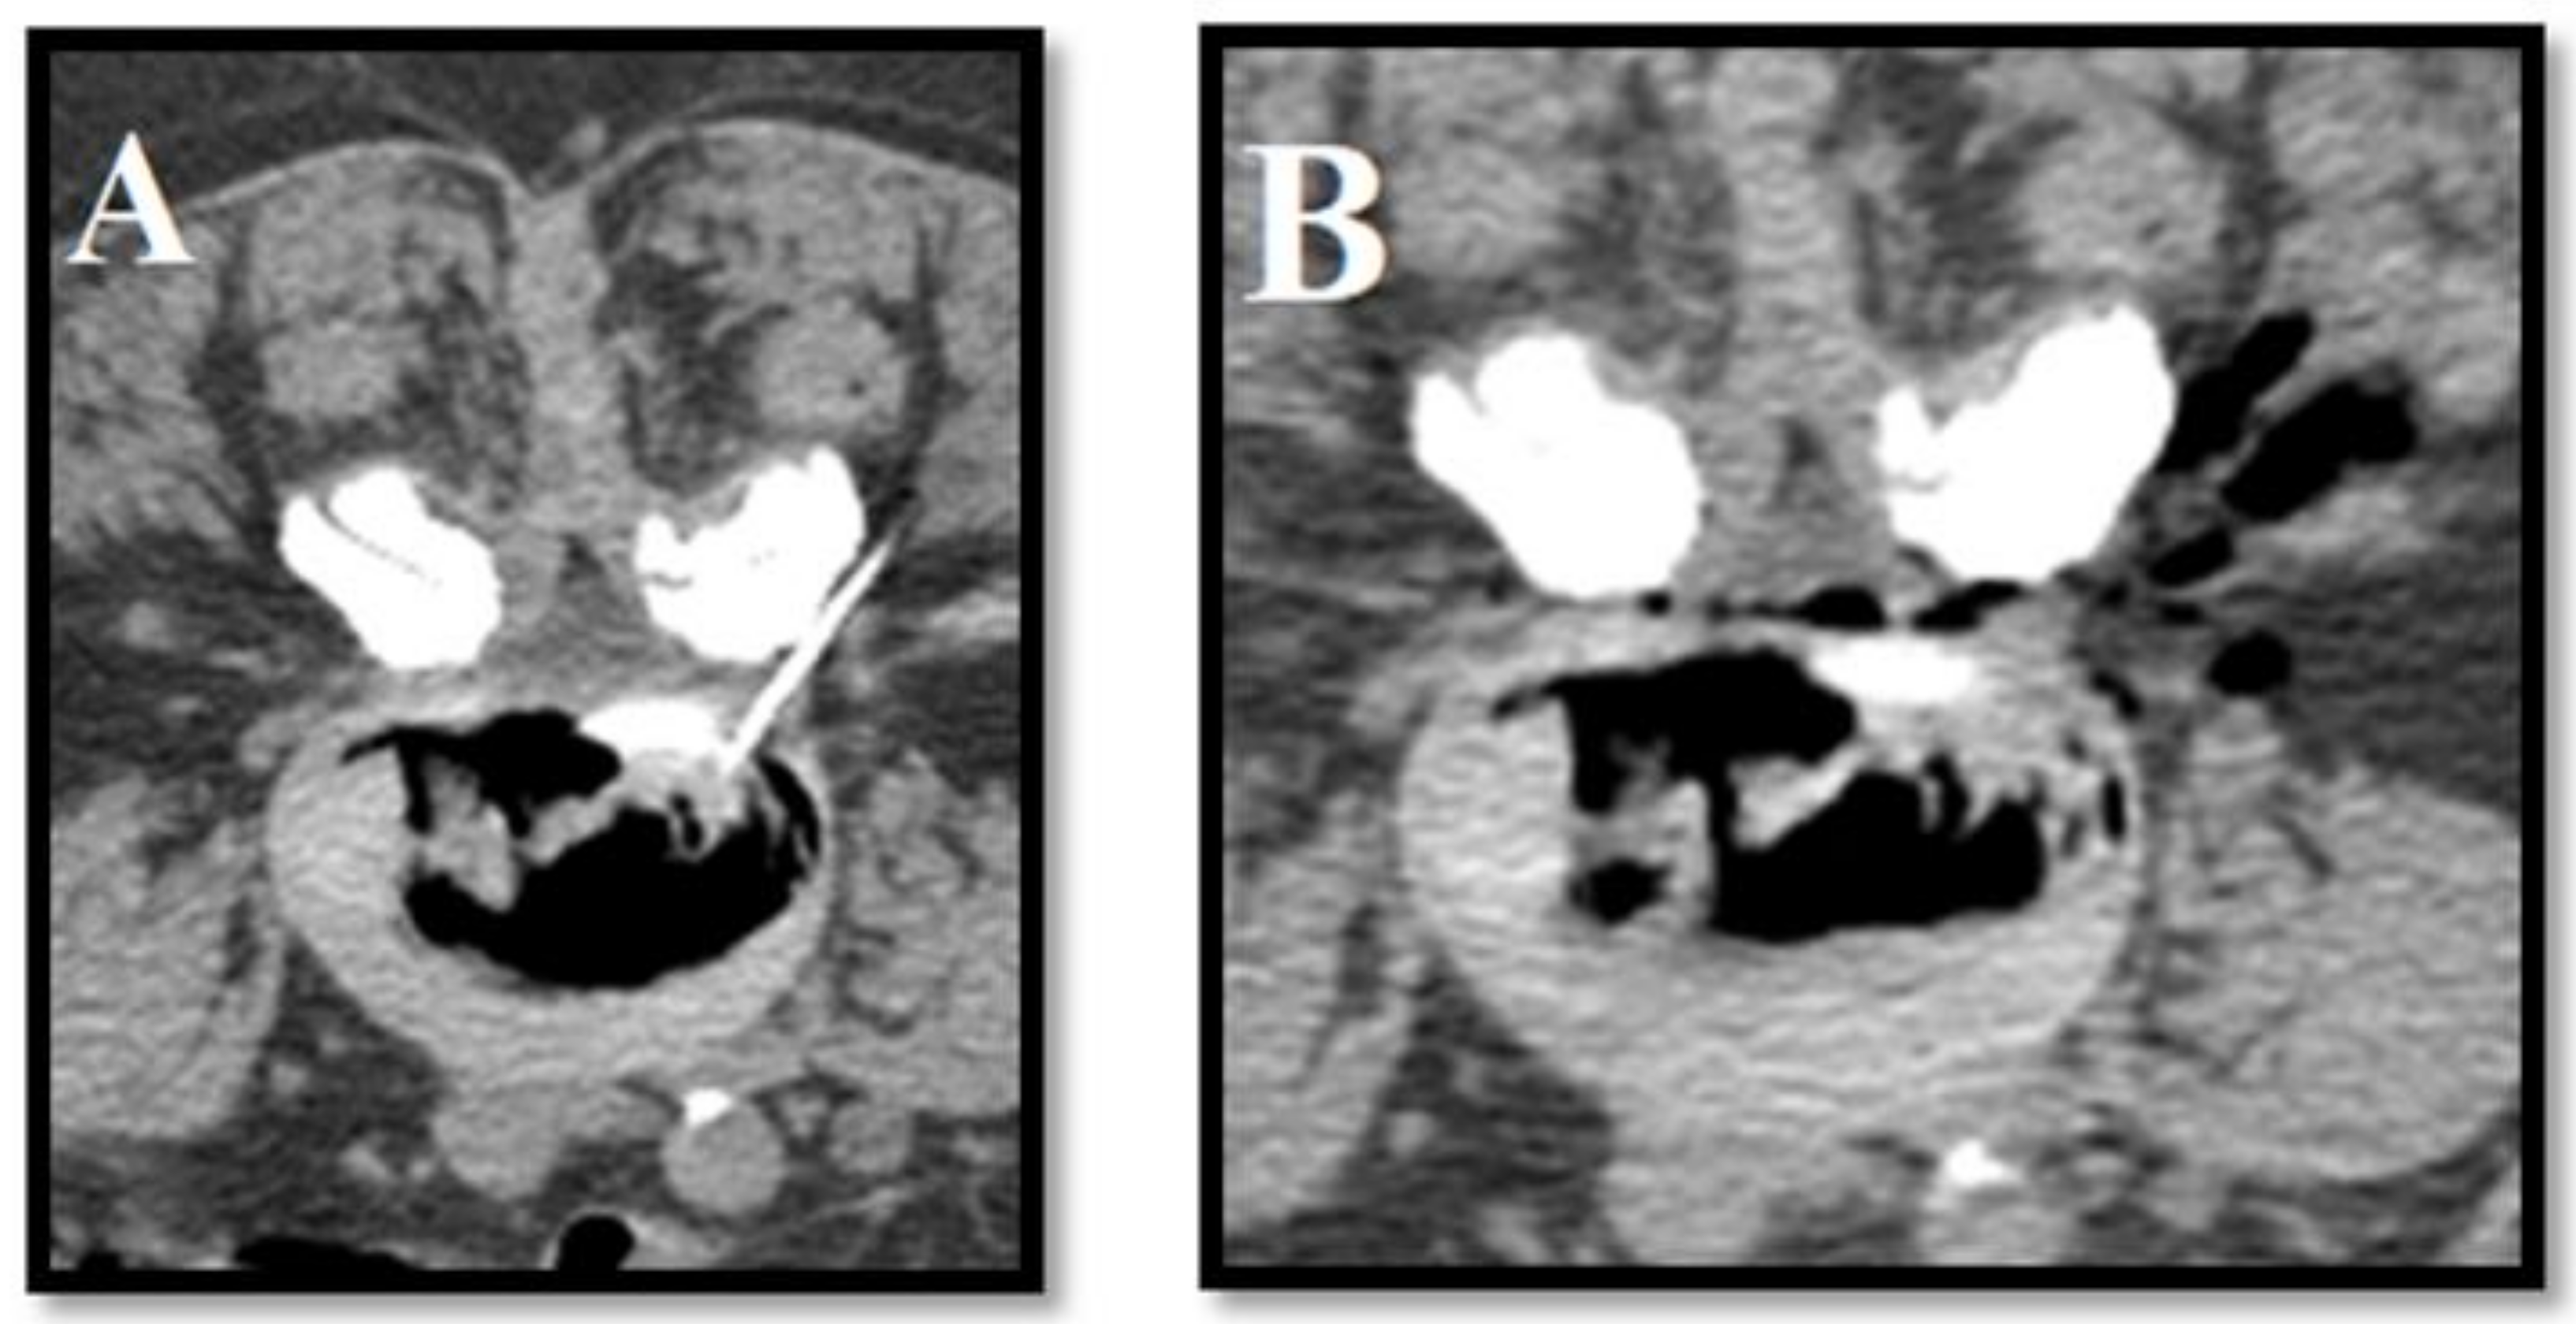

- Amoretti, N.; Huwart, L.; Marcy, P.Y.; Foti, P.; Hauger, O.; Boileau, P. CT-and fluoroscopy guided percutaneous discectomy for lumbar radiculopathy related to disc herniation: A comparative prospective study comparing lateral to medial herniated discs. Skelet. Radiol. 2013, 42, 49–53. [Google Scholar] [CrossRef]

- Ezeldin, M.; Leonardi, M.; Princiotta, C.; Dall’Olio, M.; Tharwat, M.; Zaki, M.; Abdel-Wanis, M.E.; Cirillo, L. Percutaneous ozone nucleolysis for lumbar disc herniation. Neuroradiology 2018, 60, 1231–1241. [Google Scholar] [CrossRef]